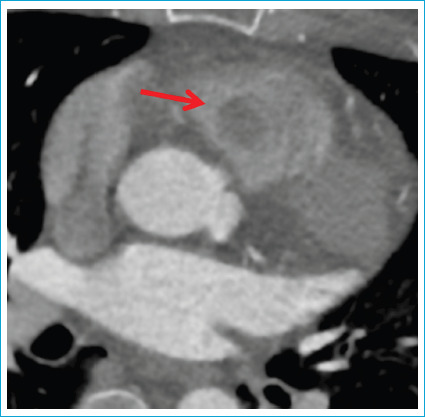

Intracardiac glomus tumors are very rare neoplasms arising from mesenchymal cells. Solitary glomus tumors are usually benign and mostly seen in the skin of limbs. Still, exceptional cases of noncutaneous visceral glomus tumors have been reported at sites other than the limbs. We present a case of glomangioma that was surgically removed from the right ventricle and briefly pointed to the importance of differential diagnosis of cardiac tumors. A 57-year-old woman was referred to our hospital for dyspnea and recurrent arrhythmia attacks. We performed a three-dimensional transthoracic echocardiogram, and contrast chest CT, which revealed a mass in the right ventricle. She was successfully treated with cardiac surgery. After pathological studies, the tumor was finally diagnosed as benign intracardiac glomangioma.